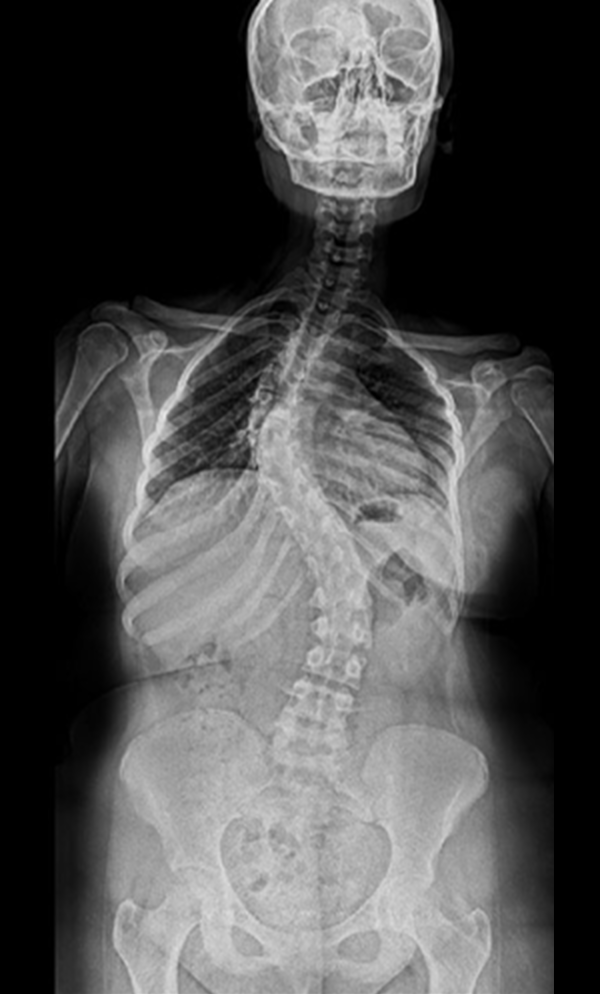

BEYOND RECOVERY : REAL STORIES

Gallery : Before - After